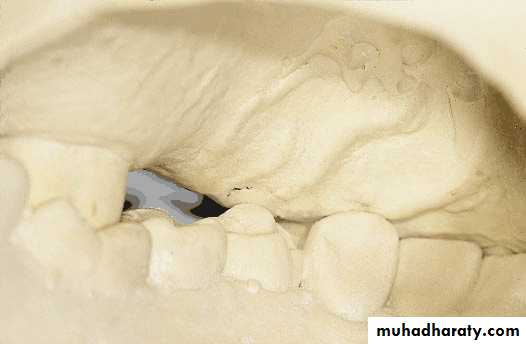

Mounting of diagnostic casts

Objective:To position the casts of dental arches on an articulator so that the casts have the same relationship as do the mandible to maxilla in the patient skull.

Three distinct phases of the procedure are

Orientation of the maxillary cast to the condylar elements of articulator by means of a face- bow transfer.4/2/2018

Orientation of the mandibular cast at the patients centric jaw relation by means of an accurate centric jaw relation record

Verification of these relationships by means of additional centric jaw relation records and comparison of occlusal contacts on the articulator with those in mouth.

Evaluation of mounted diagnostic casts

Potential problems such as insufficient inter arch distance, irregularity or mal position of the occlusal plane, extruded or malposed teeth, and unfavorable maxillomandibular relationships are more apparent in accurately mounted casts because the lips, cheeks, and skull block out good visual access to the teeth in the mouth.4/2/2018